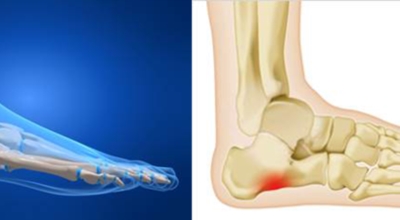

족저 근막이란 발가락 시작지점부터 발뒤꿈치뼈까지 발바닥 전체를 감싸고 있는 두꺼운 막을 말해요. 족저 근막은 발바닥 아치를 지속시켜 발바닥이 지면을 내딛음으로써 나타나는 충격을 흡수하는 중요한 역할을 수행하고 있어요. 이 족저 근막에 일차적으로 서서히 조직 손상이 일어나고 계속적인 활동으로 인해 염증이 커지면서 발 뒤꿈치 부근 통증을 유발하게 되는데 염증은 무리하고 반복적인 동작, 과도한 사용으로 마찰에 의해 발생해요.

주요 증상은 통증으로 발뒤꿈치 안쪽이 아주 아프며, 맨발로 바닥을 걸을 때 걸음을 내딛을 때마다 통증이 있어요. 가장 심한 통증은 아침에 일어나 첫 걸음을 뗄 때인데, 밤에 족저근막이 수축하다가 발에 체중이 가해지면서 갑자기 늘어나는 현상입니다.